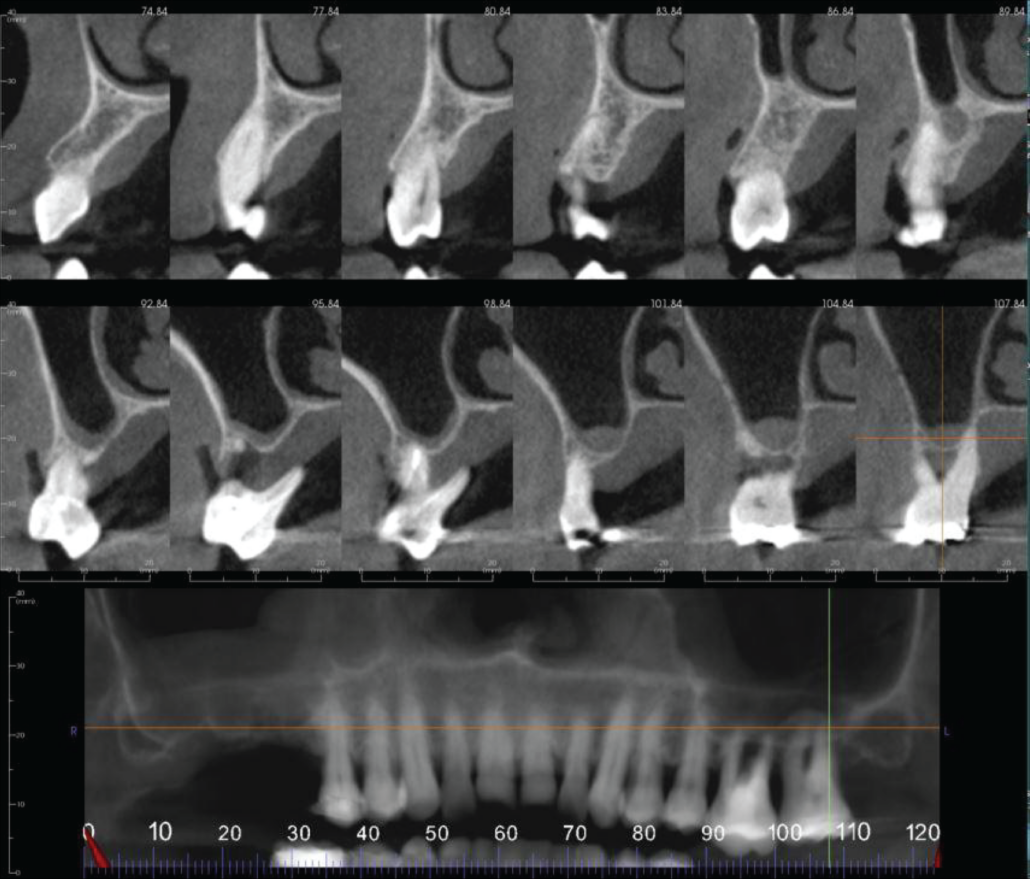

Severe periodontal disease is affecting the lower anterior teeth, UL6 and UL7 with loss of attachment of the latter.

Both TMJs have severe degenerative joint disease with condylar osteophytes and flattening of the right glenoid fossa. The left condylar head has an Ely’s cyst (also called a subcortical or subchondral cyst).

Cropped panoramic and cross sections of the UL6-7 region. The UL6 and UL7 have severe loss of alveolar bone due to periodontal disease.

Bilateral parasagittal sections of the TMJs. Both joints have severe degenerative joint disease with condylar osteophytes and flattening of the right glenoid fossa. The left condylar head has an Ely’s cyst.